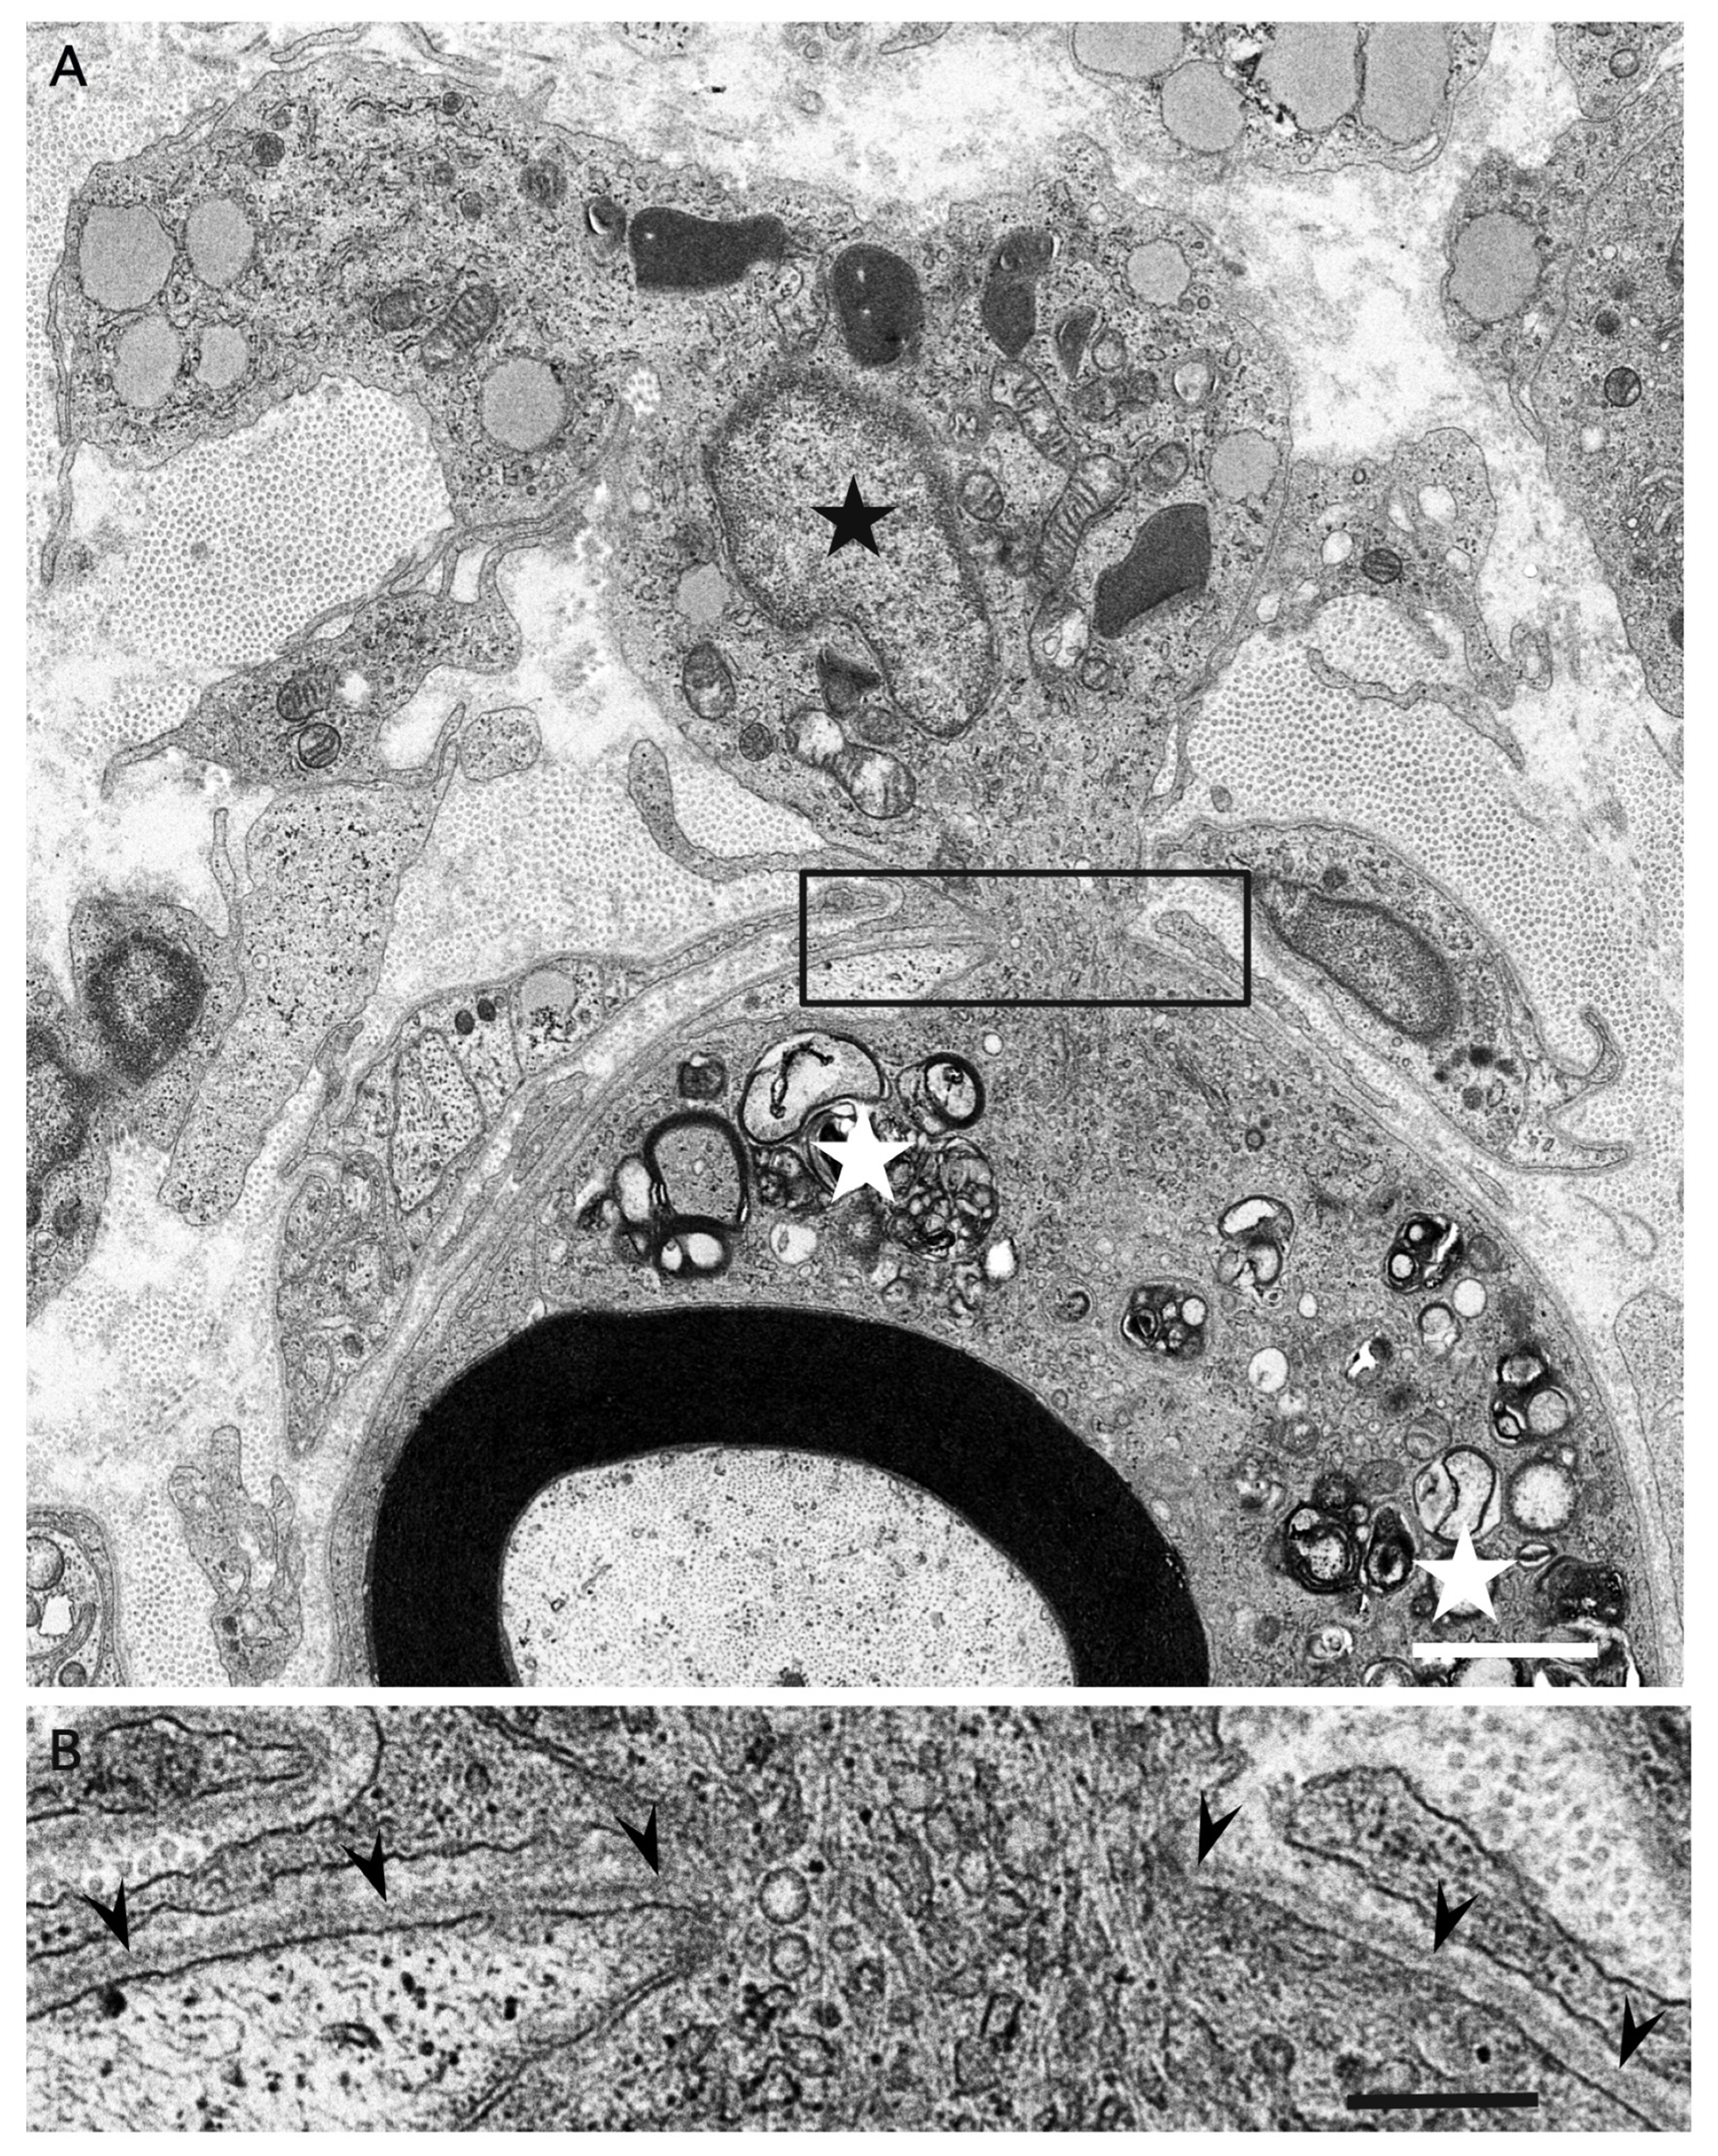

3. Morphology of Macrophages in Demyelination